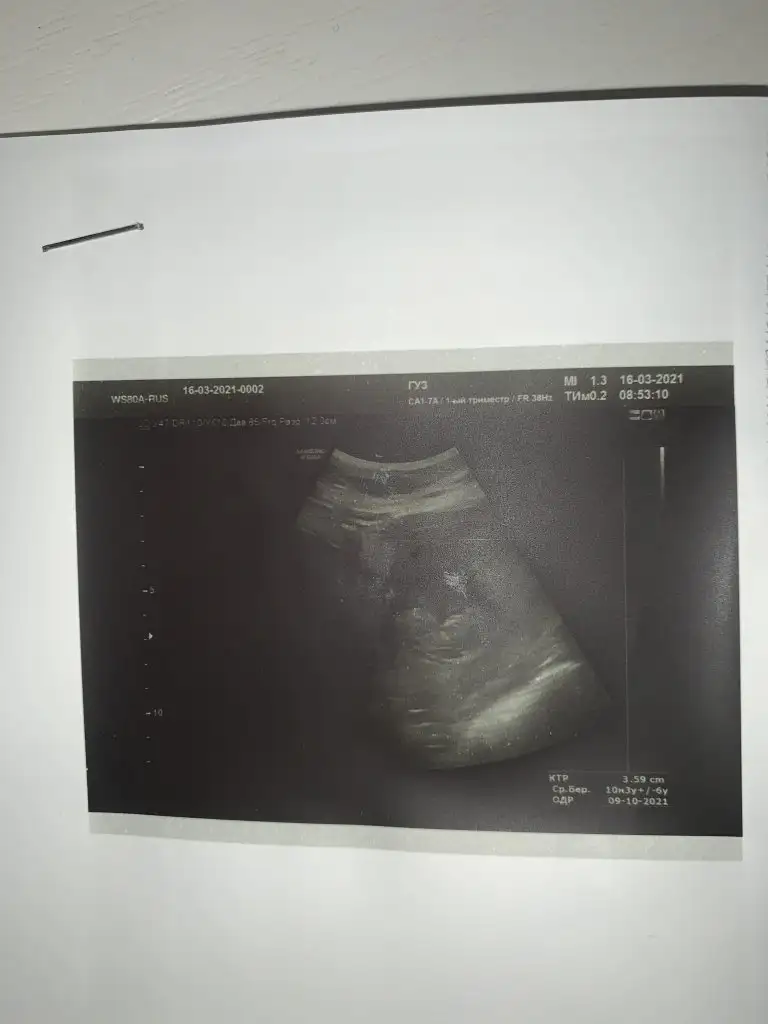

Merhaba rica ediyorum bunada bakın. Vajinal ve burada 10+3

Selisay ikinci gidişim Dr a ilki minik yuvarlak keseydi bugünkü bu nabzı 124 çıktı

Eklentiler

• IMG_20210331_155424.webp

IMG_20210331_155424.webp

25,3 KB · Görüntüleme: 1.170